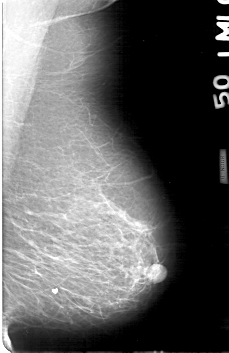

D_4170_1.RIGHT_MLO

RIGHT_MLO LINES 5251 PIXELS_PER_LINE 3421 BITS_PER_PIXEL 12 RESOLUTION 43.5 OVERLAY

FILE: D_4170_1.RIGHT_MLO.OVERLAY

TOTAL_ABNORMALITIES 1

ABNORMALITY 1

LESION_TYPE CALCIFICATION TYPE AMORPHOUS DISTRIBUTION CLUSTERED

ASSESSMENT 0

SUBTLETY 2

PATHOLOGY BENIGN

TOTAL_OUTLINES 1

BOUNDARY